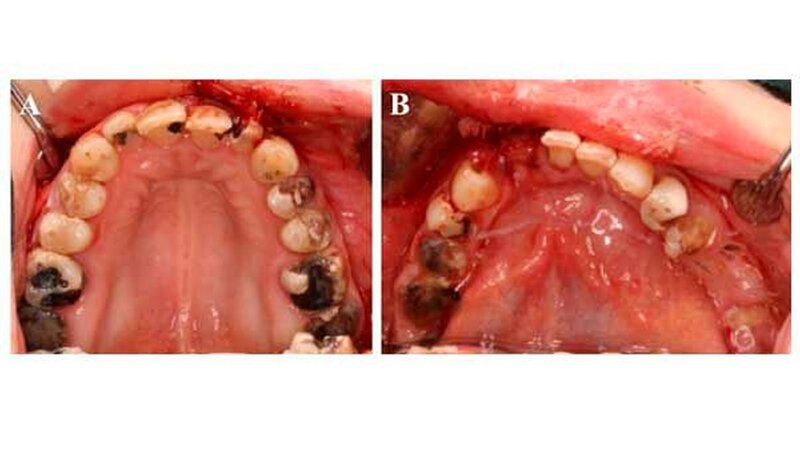

Die orale Situation einer Crystal Meth-Patientin

Die weitere klinische Inspektion ergab intraoral den Befund eines kariös tief zerstörten Restzahngebisses mit multiplen, teils gelockerten, nicht erhaltungswürdigen Zähnen.

Eine weitere Nebenwirkung ist der sogenannte Meth Mouth, der sich klinisch unter anderem durch eine Xerostomie sowie ausgeprägte kariöse Läsionen manifestiert. Zusätzlich gibt es erste Hinweise auf einen möglichen pathophysiologischen Zusammenhang zwischen einem langjährigen Konsum von Crystal Meth und der Entwicklung von oralen Knochennekrosen, die in ihrem klinischen Erscheinungsbild der Antiresorptiva- beziehungsweise der Medikamenten-assoziierten Osteonekrose der Kiefer (MR-ONJ) ähneln.